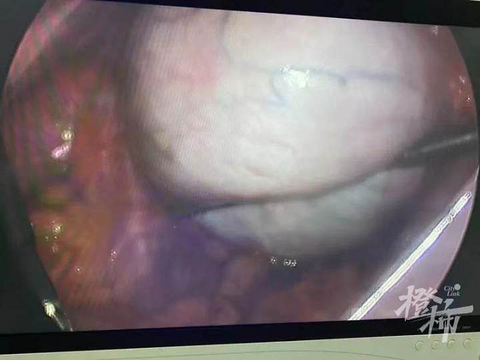

16岁女生肚子痛,医生一查惊了,15cm巨大卵巢囊肿!

16岁怎么可能会有妇科肿瘤?这可能是大多数人的疑问。但事实上,妇科肿瘤和年龄、是否有性生活没有必然联系,不仅仅是育龄女性,青春期女性也要引起重视。 近期,浙医健杭州医院(杭钢医院)接诊了一位16岁的女孩橙橙,因为肚子痛难以忍受来到急诊就诊,医生紧急做了彩超后发现盆腔内竟有15cm的巨大卵巢囊肿,并且可能已经发生囊肿蒂扭转,需要尽快手术。 妇科以最快时间为橙橙安排了腹腔镜微创手术,术中可以看到卵巢囊